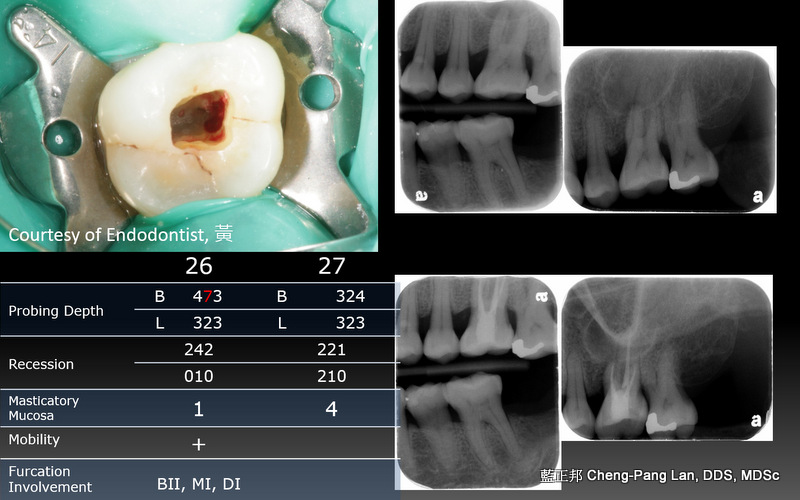

老師常常暗示著大家,implant與natural teeth之間,留下natural teeth比較好。這個我真的相信,在牙周病科的每一位學弟妹也都相信,甚至我相信週六在場的牙周病醫師都認同,但是大家有沒有想過,每隔週三一起開會的Prosthodontist、 Orthodontist都相信嗎?甚至,從實習醫師畢業就進入職場服務病人的學弟妹們,都相信嗎?